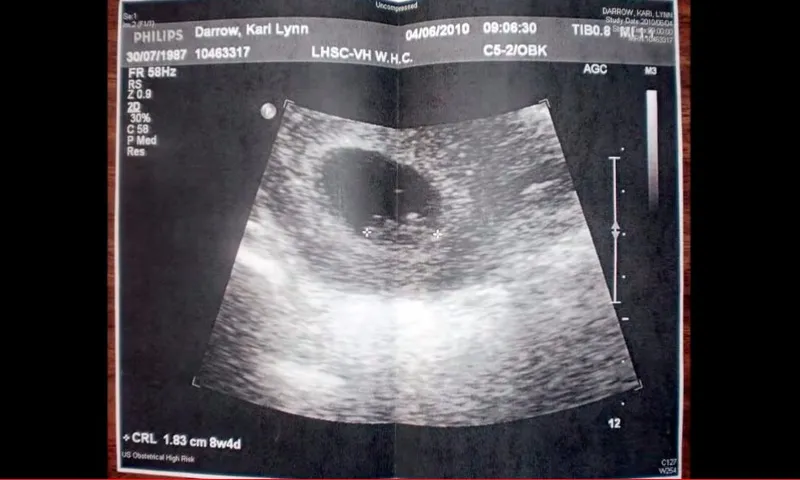

Mujer que abortó y subió video a YouTube se arrepiente: Siempre amaré a mi pequeña

Kari Lynn, una mujer canadiense que abortó y subió a YouTube los documentos relacionados al procedimiento, así como su ecografía,... Leer más